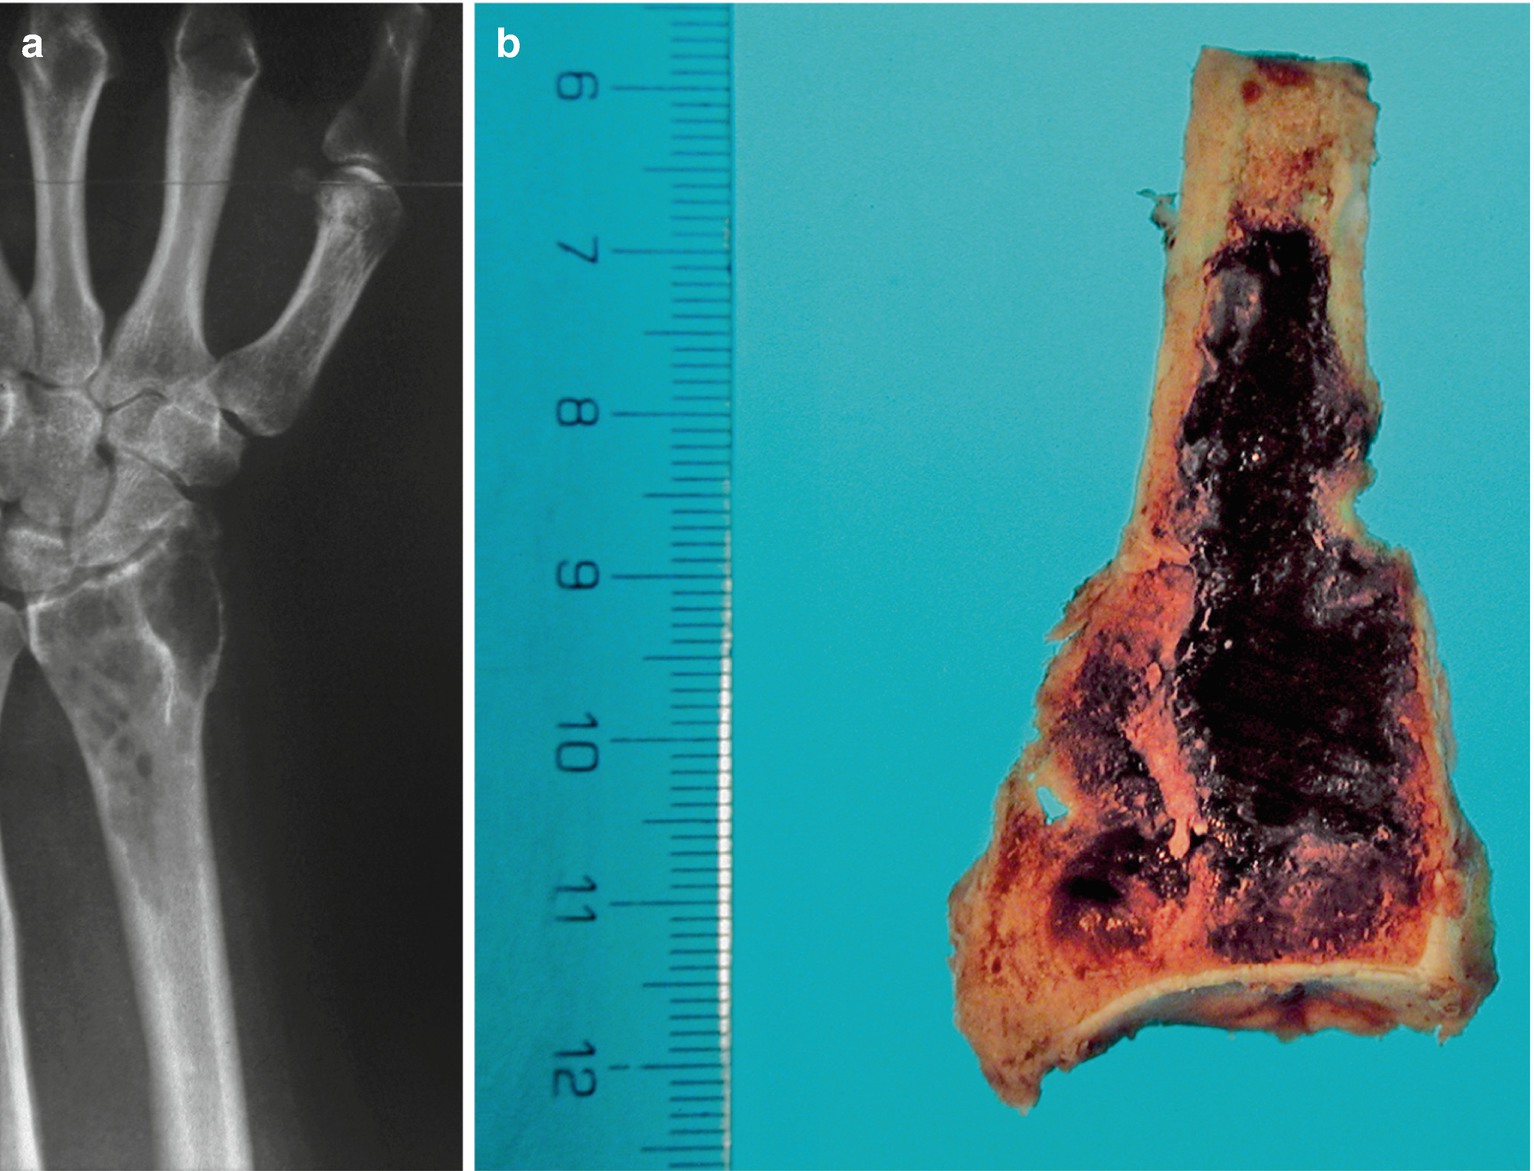

Brown Tumor Of Hyperparathyroidism Springerlink